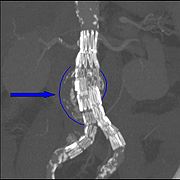

During the summer of 2006, mine had grown to 5.7. I had surgery in November using a procedure, endovascular aneurysm repair (EVAR). Endovascular repair first became practical in the 1990s.The surgeon places an abdominal aortic endoprosthesis (stent) into the expanding aorta through the groin

The aorta leading from the heart is at the top portion of the above photo. The femoral arteries in the legs are shown in the lower portion. The stent is manufactured specifically for each person with an aneurysm. It is placed into the aorta and into the femoral arteries using a catheter. Once the surgeon is happy with the placement (using many xrays), the catheter is removed and the stent expands. The stent is held in place by pressure.